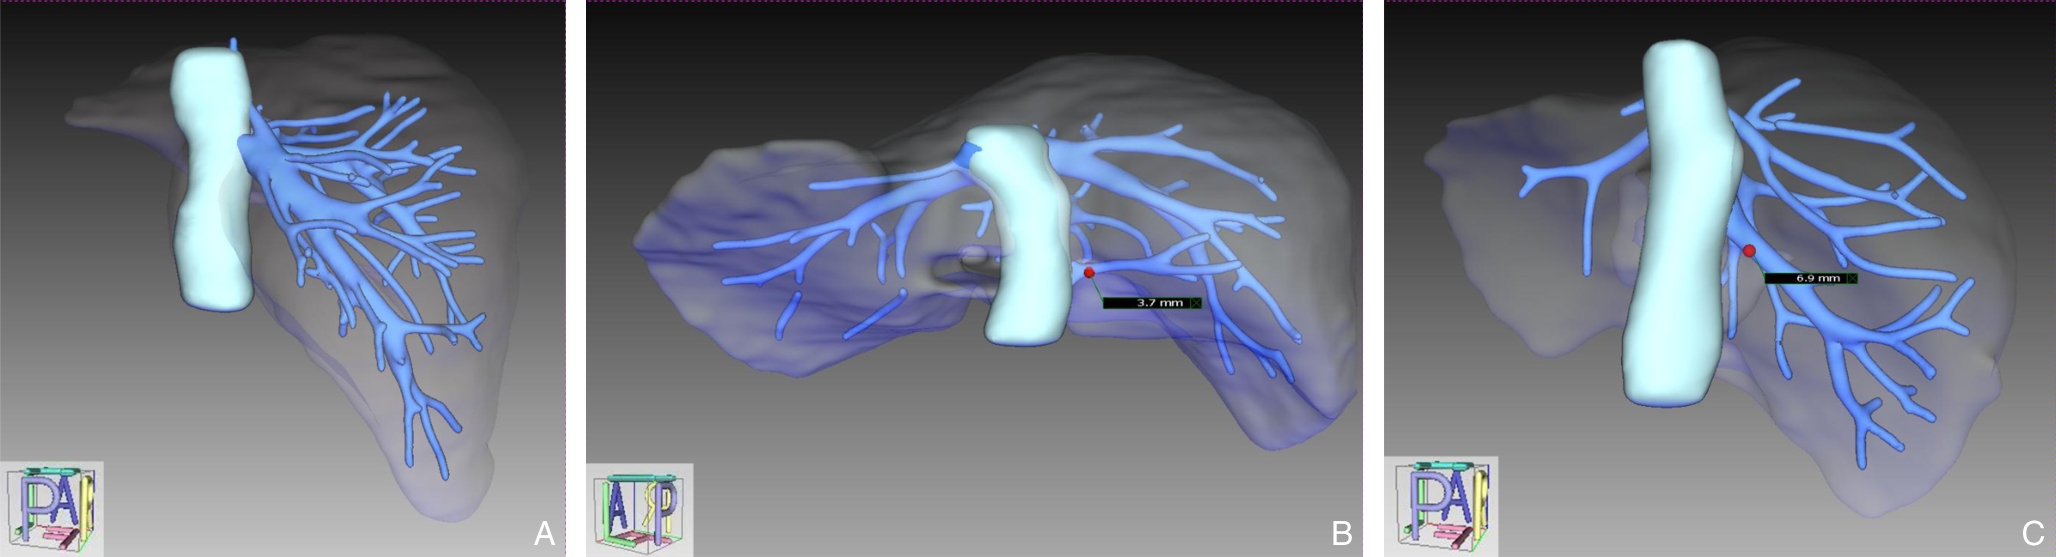

SHEN Zhengchao, CHEN Zhiyuan, XI Shihang, PAN Xuan, QIAN Daohai, MUHAMMAD Danish Irshad, WANG Xiaoming

Background and Aims Laparoscopic resection of centrally located hepatic tumors remains technically demanding due to the complex anatomical relationships with major vascular structures. Conventional intraoperative ultrasound or indocyanine green fluorescence imaging (ICG-FI) alone has limitations, particularly in visualizing deep anatomical structures. This study aimed to evaluate the clinical value of augmented reality (AR) navigation combined with ICG-FI in laparoscopic resection of central hepatic tumors.Methods A retrospective analysis was conducted on 38 consecutive patients who underwent laparoscopic resection of central hepatic tumors guided by AR navigation combined with ICG-FI between May 2022 and March 2025. Intraoperative navigation performance, surgical parameters, and perioperative outcomes were assessed.Results All 38 procedures were completed laparoscopically without conversion. The intraoperative tumor fluorescence detection rate was 100%. The mean operative time was (324.9 ± 132.4) min, and the median intraoperative blood loss was 400 (50-1 200) mL. The mean registration error was (6.3±0.6) mm. The median number of predicted and verified vessels was 6 (4-8) and 7 (5-10), respectively. R0 resection was achieved in all patients, with a mean surgical margin of (1.5±0.5) cm. The postoperative complication rate was 13.2%, with no severe complications such as intra-abdominal hemorrhage, gas embolism, or liver failure. The median postoperative hospital stay was 9 (4-20) days. During a median follow-up of 20 months, no tumor recurrence was observed.Conclusion The combined use of AR navigation and ICG-FI enables intraoperative prediction and verification of critical vascular structures and facilitates precise control of the transection plane in laparoscopic resection of central hepatic tumors. This technique improves surgical precision and safety and shows promising clinical potential.